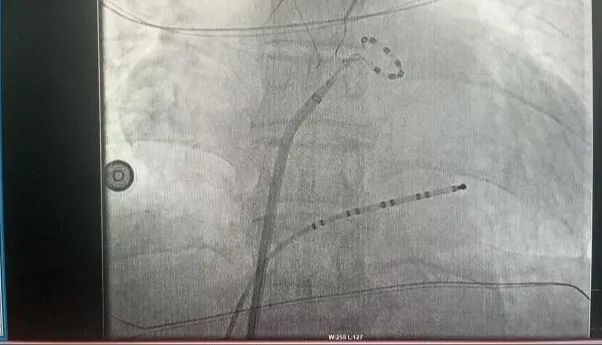

近日,延安大學(xué)咸陽醫(yī)院成功實(shí)施了咸陽地區(qū)首例脈沖場消融術(shù)、首例脈沖場消融+左心耳封堵“一站式”治療房顫手術(shù)2例手術(shù)的順利完成,標(biāo)志著我院在心律失常治療技術(shù)上的又一重大突破!

此次手術(shù)患者均為持續(xù)性房顫患者,由延安大學(xué)咸陽醫(yī)院吳棟梁院長、心律失常專家劉雄濤副院長帶領(lǐng)介入團(tuán)隊(duì)開展,安全高效、圓滿完成手術(shù),手術(shù)過程患者全程清醒,術(shù)中自訴感覺良好,無痛苦感受。術(shù)后患者的心律恢復(fù)并維持了竇律,目前恢復(fù)情況良好,無任何并發(fā)癥出現(xiàn)。